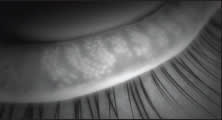

■ Meibomian gland duct probing, a procedure to mechanically open obstructions postulated to occur at the orifice and within the lumen of the meibomian gland, is a novel approach first described by Dr. Steven Maskin (Figures 1 and 2).7 Since 2009, published reports of several small series of patients suggest a substantial percentage of patients experience subjective relief of symptoms, lasting for months. In a 2011 AAO presentation, Dr. Maskin reported 33% of original series of patients required retreatment at an average of 10 months. Challenges of this procedure include achieving good lid anesthesia for the procedure, which is somewhat uncomfortable, and also determining when retreatment is appropriate. Dr. Maskin has found his patients are well anesthetized and tolerate the procedure with the use of jojoba-containing anesthetic ointment containing 8% lidocaine. The jojoba wax esters appear to increase delivery of anesthetic into the meibomian glands.

Figure 2. Maskin Probe inside MG of a patient with reconstructed lid and obstructive meibomian gland dysfunction. COURTESY OF STEVEN MASKIN, MD